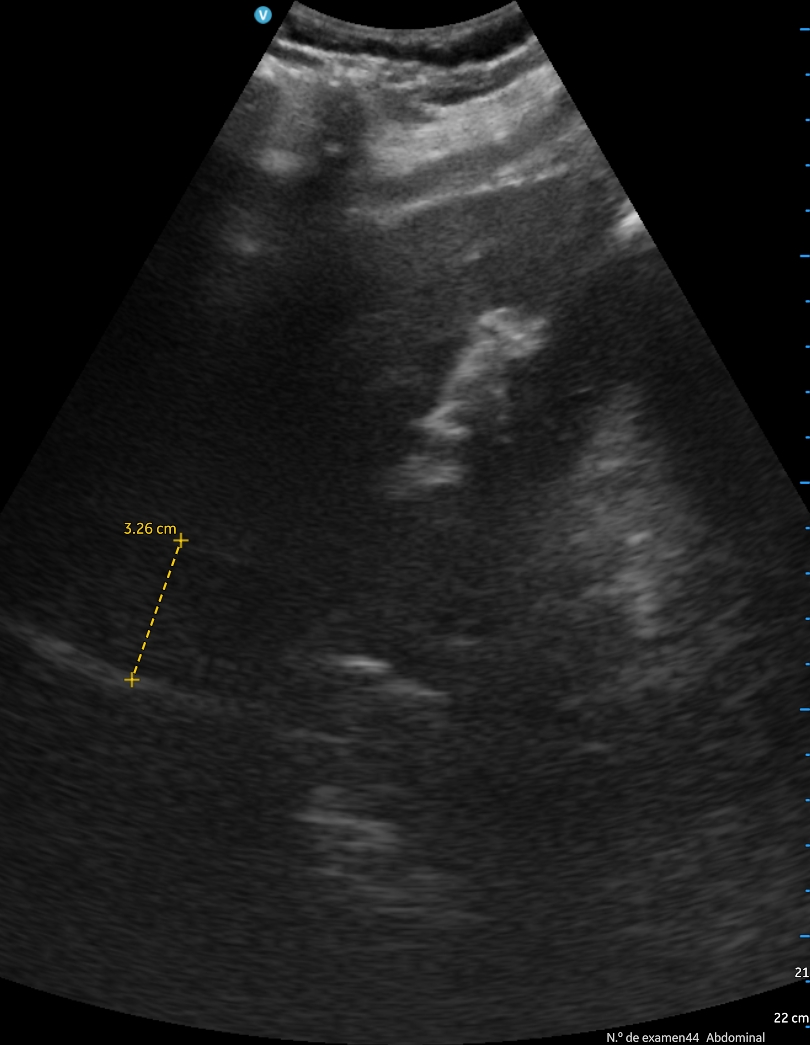

A los 2 días, el paciente presenta empeoramiento de clínica, con disminución SpO2 a 90%, persistencia de fóvea intensa y disnea de reposo. Se revalora ecográficamente encontrando aumento de derrame pleural, ahora 500 cc, una vena cava de 3,27 cm no colapsable y derrame pericárdico. Finalmente se decide derivación hospitalaria.